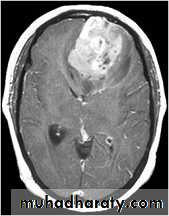

Meningioma

Benign tumor arise from the arachnid cells of the meningeal covering of the brain are most common primary intracranial neoplasm

Usually present in middle age female

it is well defined extra axial , located mainly at the convexity of the skull periphery

CT finding

meningioma presented as isodense area or slightly hyper density area with surrounded crescent of hypo density ( csf cap ) post contrast injection the lesion enhance homogeneously with enhancing Dural tail .

20 % show calcification

hyperostosis & thickening of the near by bony part of the skull & diplioc space .

it may be associated with little or no peri focal edema .

if the lesion associated with central necrosis with large perifocal edema meningio sarcoma should be excluded .